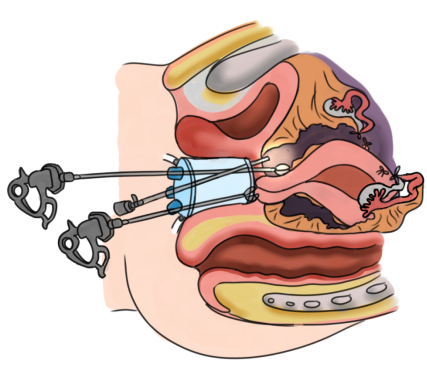

59岁绝经女性,因子宫肌瘤合并阴道前壁膨出至黔南州人民医院就诊,需行全子宫切除手术治疗。术前评估患者存在盆腔粘连,行阴式子宫切除手术因暴露问题,有脏器损伤的风险。因此,妇科主任黄燕、副主任王朝志带领科室团队反复研究和讨论,最终确定为患者施行经阴道单孔腹腔镜下全子宫及双附件切除术,并利用自身韧带行盆底重建手术。此次为患者实施的经阴道单孔腹腔镜下全子宫双附件切除手术,是黔南州人民医院妇科团队首次实施。经阴道单孔腹腔镜手术是指经阴道对妇科疾病进行治疗的微创腔镜手术,手术切口选择在阴道最深处,打开阴道穹隆置入腹腔镜的器械完成手术操作,是继传统腹腔镜、经脐单孔腹腔镜后微创手术的“升级版”。

经阴道单孔腹腔镜下全子宫双附件切除手术,手术难度大,主要在于术中操作倒切,即先切除子宫骶主韧带及血管等,再切除双侧附件。经阴道单孔腹腔镜在气腹建立后,盆腹腔脏器清晰可见,可用超声刀分离粘连,较传统经阴道手术暴露更加清楚,避免了粘连导致的脏器损伤。

另外,经阴道单孔腹腔镜产生的“筷子”效应,即由于手术中腹腔镜镜体和操作器械都是经单一切口进入腹腔,容易造成器械之间在腹腔内外的相互干扰,也为手术增加了难度。